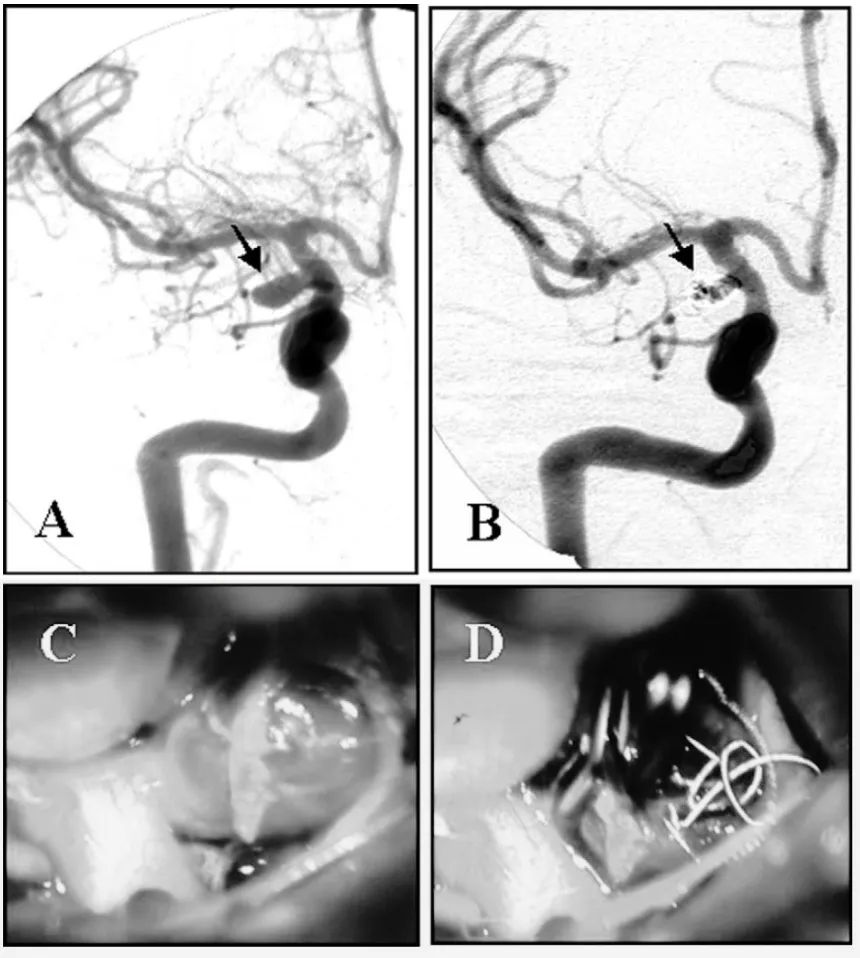

本研究中记录了两个典型病例。一位31岁女性,因右侧后交通动脉动脉瘤破裂导致蛛网膜下腔出血,GDC栓塞后两周的随访造影提示瘤颈仍有明显残余充盈,鉴于动脉瘤的大小和形态无法再填入弹簧圈,最终经右侧翼点入路完成夹闭并取出弹簧圈,术后2个月重返工作。

(A)右侧颈内动脉(ICA)血管造影显示右侧后交通动脉动脉瘤(箭头所示)。

(B)栓塞术后2周血管造影显示动脉瘤瘤颈残余(箭头所示)。

(C)术中照片显示动脉瘤囊被弹簧圈扩张。

(D)动脉瘤已夹闭,并经动脉瘤壁取出弹簧圈。